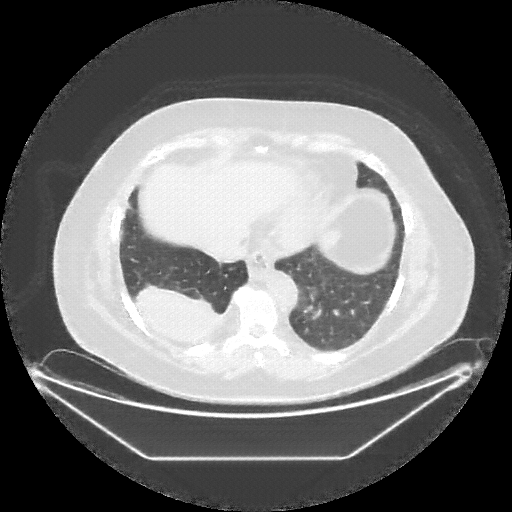

Reconstructed NATIVE CT scan (cycle consistency)

Full window (WL 1023.5, WW 4095 β†’ Low βˆ’1024, High +3071)

Lung window (WL -600, WW 1500 β†’ Low βˆ’1350, High +150)

Mediastinum window (WL 40, WW 400 β†’ Low βˆ’160, High +240)